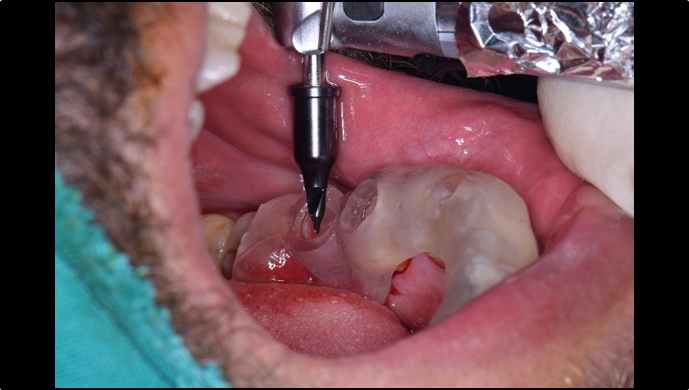

Clinical case: : Immediate loading of lower molars using R2Gate prefabricated 3D-printed provisional restoration

- Courtesy of Dr. Sam Omar, Egypt -